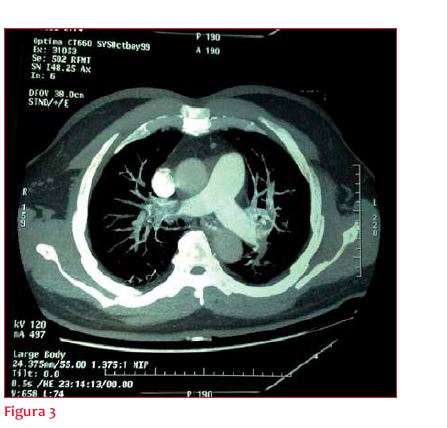

Paraclínica: función renal, gasometría e ionograma normales. No se solicitaron biomarcadores cardíacos. Angiotomografía de tórax: (figura 3) se observan imágenes de defecto de relleno a nivel de la rama derecha de la arteria pulmonar y en las ramas lobares y segmentarias de todos los lóbulos bilateralmente, compatibles con tromboembolismo pulmonar (TEP). Eco Doppler venoso de miembros inferiores (MMII): sin evidencias de TVP.